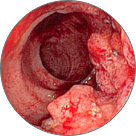

ДО ШТО МОЖАТ ДА ДОВЕДАТ ХЕМОРОИДИТЕ?

Фекална инконтиненција

Тромбоза на хемороидалните јазли со локална некроза на ткивото

Венозна стаза во патолошки изменети проширени вени

Крвавење од потслизестите крвни садови, што доведува до некроза на ткивото и анемија

Ректален карцином